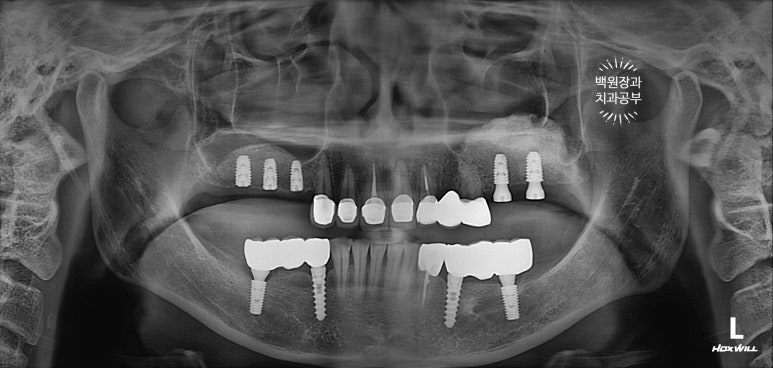

앞니와 어금니를 완성해두고 치과용 파노라마 엑스레이를 찍어봅니다.

새로 만들어진 보철물이 경계도 자연스럽게 잘 형성되어있고, 잇몸뼈와 조화롭게 완성이 되었네요.

정말... 다시봐도 상악동 뼈이식술이 아주 적절히 잘 되어 딱 필요한만큼만 되어있네요. ㅎㅎ 이럴때 정말 뿌듯합니다. (변태같나요!?)

가장 보람을 느끼게 되는 보철물 완성 후 치과용 파노라마 사진입니다.

정갈하게 치아가 완성되었네요... 이런 맛에 치과의사 하는 것이 아닌가 싶습니다.

뼈가 너~무 얇아 임플란트를 해드릴 수 없었던 송곳니 부위는 지르코니아 브릿지로 제작함으로써 자연스럽게 마무리 되었습니다.